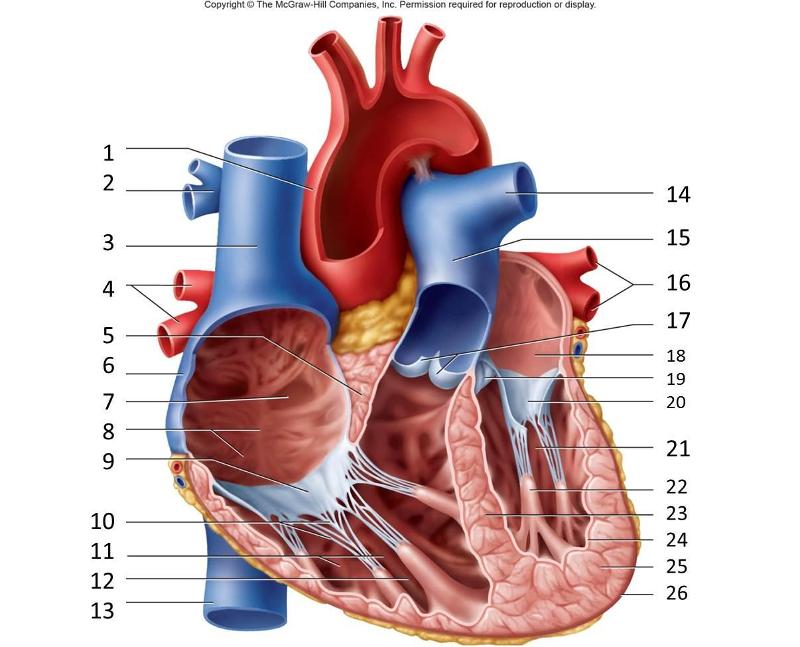

Anterior interventricular valve

Aortic Valve (=left semilunar)

Chordae tendineae

Coronary sinus

Endocardium

Epicardium

Left atrioventricular (=bicuspid, =mitral) valve

Left/right atrium

Left/right auricle

left/right ventricle

Myocardium

Papillary muscles

Pectinate muscles

Pulmonary trunk

Pulmonary valve (=right semilunar)

Right atrioventricular (=tricuspid) valve

Superior/inferior vena cava